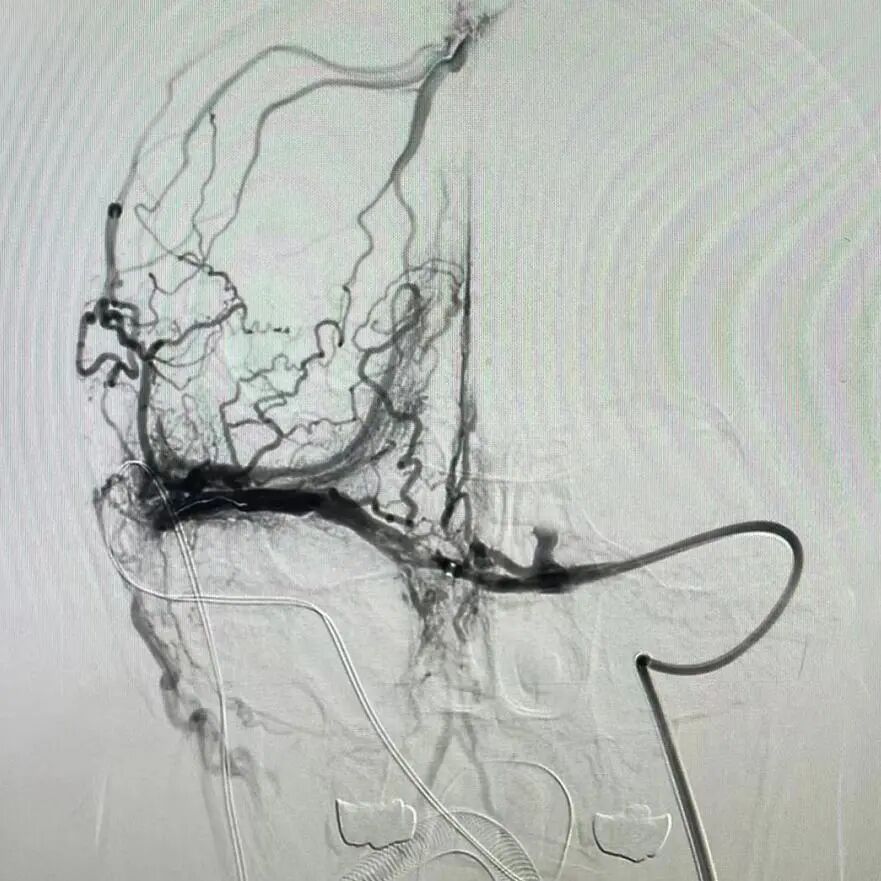

诊断明确后,两名患者均接受了正规的抗凝治疗。但颅内静脉窦血栓形成是一种临床少见,具有较高的致残、致死率的脑血管疾病。这两名患者很快便出现了脑疝症状。副院长高阳组织了神经外科、介入科、麻醉手术科、神经内科等相关科室联合急会诊,会诊专家们仔细研究讨论病例后,提出了全麻下颅内静脉窦血栓介入取栓术的治疗方案。盐城市一院神经内科主任医师任桃杰向患者及家属讲解了详细的治疗方案,先后为两名患者实施了颅内静脉窦血栓介入取栓术。手术时长约3小时,术中取出大量血栓,术后造影提示被堵塞的静脉窦血流通畅,术后3天患者意识障碍均逐渐好转,头痛、呕吐等症状明显缓解,取得良好手术治疗效果。术后约10天,患者均能下床自主活动。不久后,两名患者均康复出院。